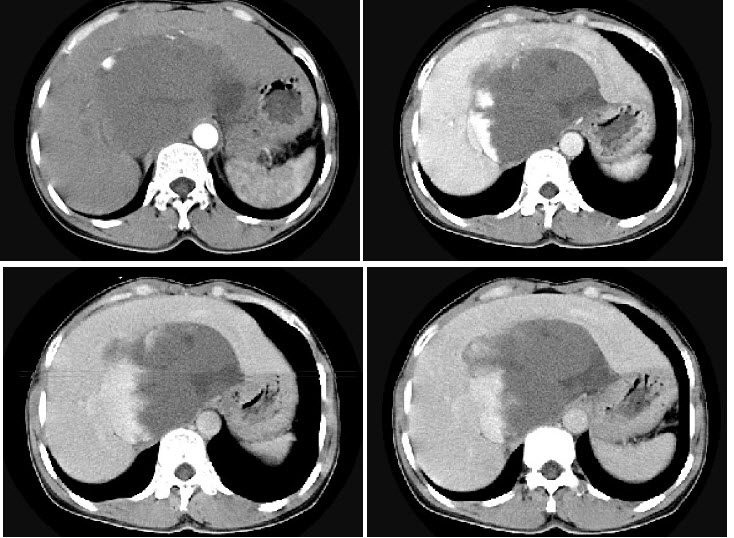

A.右侧输尿管下段管壁增厚,管腔狭窄

男,36岁,腹胀、消化不良、消瘦、中上腹痛,影像检查如下图,最可能的诊断是()

A.胃间质肉瘤并肝转移

B.胃间质瘤并原发性肝癌

C.内胚窦瘤肝转移

D.胃淋巴瘤伴原发性肝癌

E.胃间质瘤并肝血管瘤